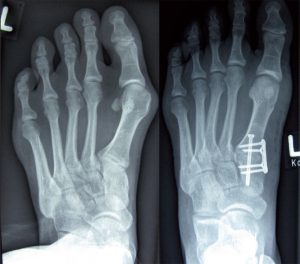

Röntgenbild Hallux valgus